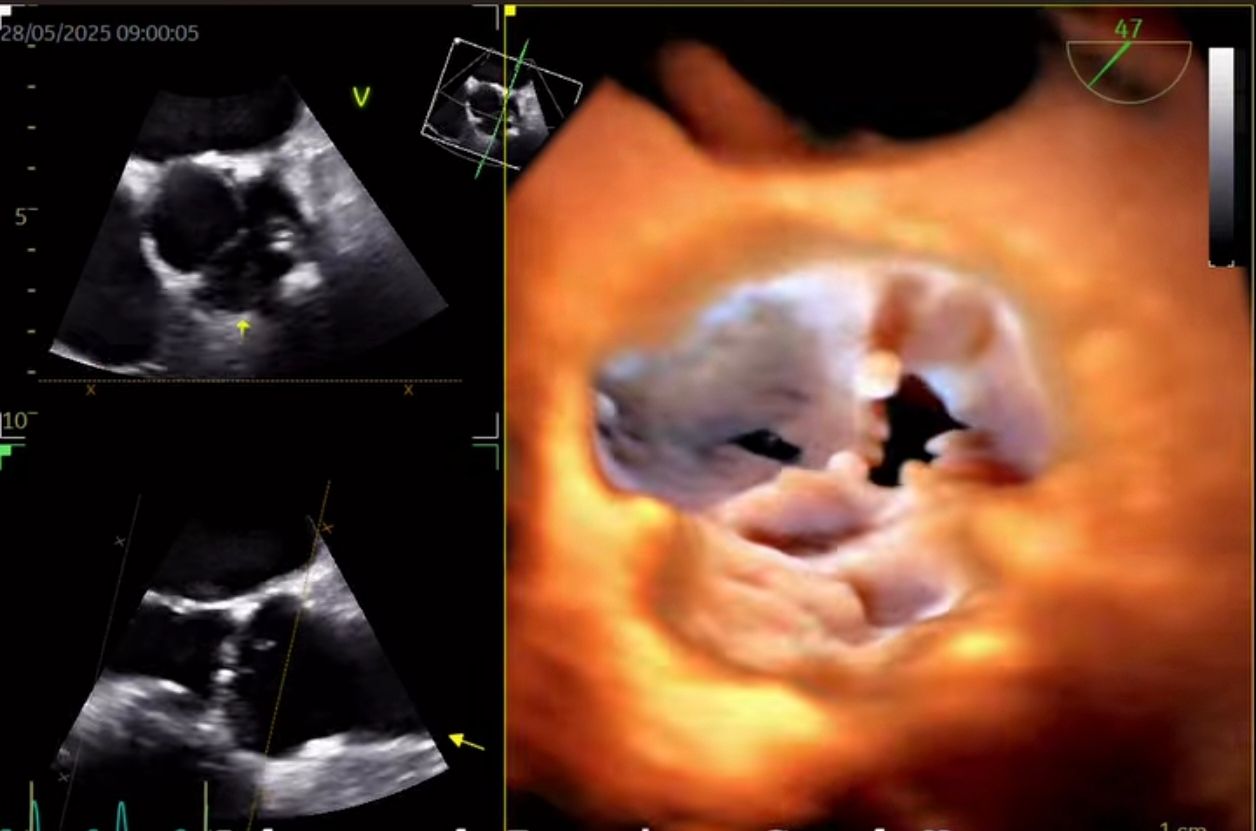

Soy el Dr. José Alberto Sánchez Toscano, con una subespecialidad en Cardiologia (2021-2023) y una alta especialidad en ecocardiografía transtoracico tridimensional en adultos (2024-2025). Egresado del Instituto Nacional de Cardiología "Ignacio Chávez" y certificado por el consejo mexicano de Cardiologia. Diplomado en Patología aórtica en la práctica clínica por la Universidad de Alcalá, Valencia 2023-2024).

Misión Profesional Como médico especialista en Cardiología y Ecocardiografía bidimensional y tridimensional, mi misión es brindar atención cardiovascular de alta precisión, combinando tecnología avanzada con un enfoque humano y personalizado. Me dedico a prevenir, diagnosticar y tratar enfermedades del corazón con excelencia médica, ayudando a cada paciente a comprender su salud cardiaca y tomar decisiones informadas. Busco generar confianza, bienestar y resultados concretos, promoviendo evaluaciones ecocardiográficas detalladas y confiables que pueden marcar la diferencia en el cuidado oportuno del corazón.

• Ecocardiografía